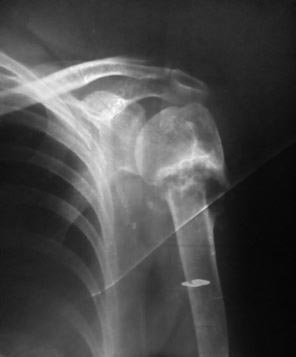

[Ortho] Несращение проксимального отдела плеча

Добрый день. Пациентка 55 лет. Мед. работник. Травма 2,5 месяца назад.

Лечилась консервативно.

На сегодняшний день беспокоит болезненность при движении рукой и

небольшая деформация по передней поверхности плечевого сустава. Какие

мнения будут по тактике лечения?